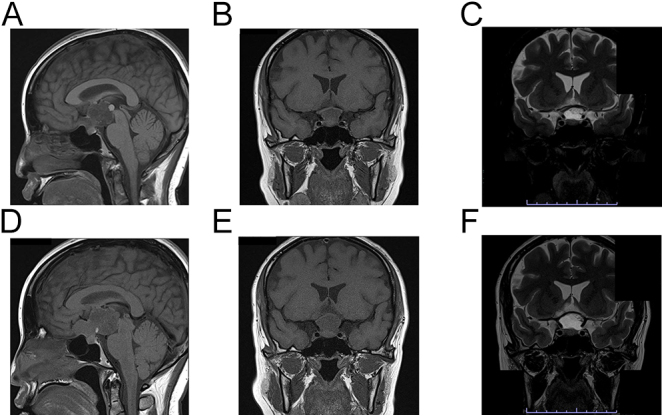

摘要:本报告描述了一个37岁的妇女在怀孕期间被诊断为颅咽管瘤的病例。患者最初在妊娠15周出现视力障碍,MRI显示囊性鞍上肿瘤。内分泌评价提示中枢性甲状腺功能减退,08:00 h基础皮质醇不能明确排除中枢性肾上腺功能不全,因为患者已怀孕且开始使用氢化可的松治疗。开始使用氢化可的松10 mg/天,左旋甲状腺素25µg/天,但21周时视力迅速恶化和多尿需要手术干预。在妊娠中期,她成功地接受了经蝶腔手术治疗。术后第7天根据基线值评估肾上腺功能,但考虑到妊娠期间的风险,维持氢化可的松。术后6周,重新评估垂体激素,继续使用氢化可的松、左甲状腺素和去氨加压素。精氨酸抗利尿素缺乏症的诊断是基于多尿、低张力尿和对去氨加压素的反应,因为术前和术后的正式检测都是高风险的。术后监测内分泌状况,妊娠进展顺利。她在怀孕38周时接受了选择性剖宫产手术。产后6个月,MRI显示残留肿瘤沿垂体柄向右视交叉延伸。产后9个月,患者出现持续性中枢性甲状腺功能减退、性腺功能减退和新诊断的成人生长激素缺乏症。正常的肾上腺功能允许停止氢化可的松。生长激素治疗计划等待肿瘤评估。本病例强调了多学科治疗妊娠期颅咽管瘤的重要性,包括产科、神经外科和内分泌学。学习要点:无论是否有妊娠计划,中枢性性腺功能减退都应该通过脑MRI检查来确定其病因,包括颅咽管瘤或其他鞍区/鞍旁病变的潜在存在。如果颅咽管瘤在怀孕期间扩大并导致视力损害,可以通过多学科合作进行手术干预。全垂体功能低下患者的分娩方式应通过产科医生和内分泌学家的多学科咨询仔细确定,并考虑计划剖宫产作为一种潜在的选择。

Summary: This report describes the case of a 37-year-old woman diagnosed with a craniopharyngioma during pregnancy. The patient initially presented with visual impairment at 15 weeks of gestation, and MRI revealed a cystic suprasellar tumor. Endocrine evaluation indicated central hypothyroidism, and central adrenal insufficiency could not be definitively ruled out based on a basal 08:00 h cortisol, as the patient was pregnant and treatment with hydrocortisone was initiated empirically. Hydrocortisone 10 mg/day and levothyroxine 25 µg/day were initiated, but rapid visual deterioration and polyuria by 21 weeks necessitated surgical intervention. She underwent successful treatment with endoscopic transsphenoidal surgery during the second trimester. Adrenal function was assessed on postoperative day 7 based on baseline values, but hydrocortisone was maintained given the risk during pregnancy. At 6 weeks after surgery, pituitary hormones were reassessed, and hydrocortisone, levothyroxine, and desmopressin were continued. Arginine vasopressin deficiency was diagnosed based on polyuria, hypotonic urine, and response to desmopressin, as formal testing was high risk both before and after surgery. Postoperatively, endocrine status was monitored, and pregnancy progressed uneventfully. She underwent an elective cesarean section at 38 weeks of gestation. At 6 months postpartum, MRI revealed residual tumor along the pituitary stalk extending from the right optic chiasm. At 9 months postpartum, the patient had persistent central hypothyroidism, hypogonadism, and newly diagnosed adult GH deficiency. Normal adrenal function allowed discontinuation of hydrocortisone. GH therapy was planned pending tumor assessment. This case underscores the importance of a multidisciplinary approach involving obstetrics, neurosurgery, and endocrinology in managing craniopharyngiomas during pregnancy.